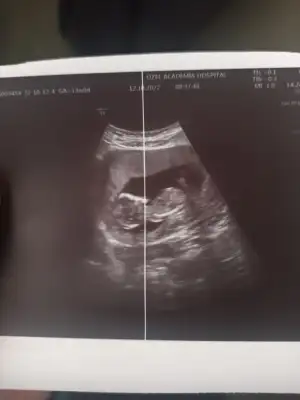

Kizlar kizlarr ben geldim. Kontrolüm vardi ense kalınlığına baktı doktor çok şükür normalmiş. Bı sıkıntı görmedi gelişimi ile ilgili. Bebisim de çok tatlı hareket ediyordu 🥰 cinsiyetle ilgili de bi tahminde bulundu erkeğe benziyor dedi küçük bı çıkıntı gördüm dedi. İlk oğlumda bu haftalarda çok daha net belliydi ben de görmüştüm ama bunu görmedim doktor gördü. Kesin konuşmuyorum bazen bu haftalarda kızlarda da böyle çıkıntı olabiliyor dedi ama ben yine de erkeğe benzettim dedi hayırlısı olsun artık sağlıklı olsun da ♥️

ayy ne güzel, nasıl kesin denildi çok mu net cıktı ultrasonda merak ettm, varsa usg atarmısınız kıyas adına:)

Bebeğimiz ayaklarını üst üste atmıştı 🤭 o yüzden doktorum çok net girebildi